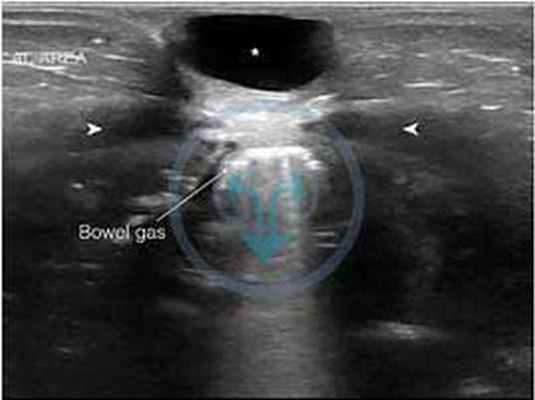

Незаращенный участок протока и является его кистой, за счет того, что она содержит застойную мочу, слущенный эпителий. Чаще она располагается ближе к пупку. Как правило, клинически себя никак не проявляет. Может быть случайной находкой при проведении планового УЗИ органов брюшной полости.

![]()

Эхограмма кисты урахуса

Для уточнения диагноза выполняется УЗИ и, в некоторых случаях, компьютерная томография.